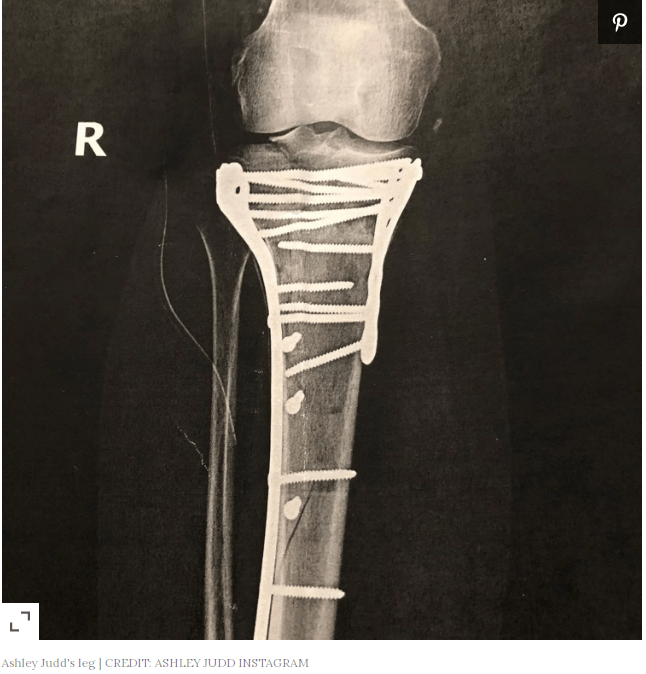

“It was broken in four places and had nerve damage,” she recalled of her leg. “Dieumerci (‘Thanks be to God’) remained seated, without fidgeting or flinching, for 5 hours on the rain forest floor. He was with me in my primal pain. He was my witness.”

After the 52-year-old actress made it out of the jungle in the Democratic Republic of the Congo (DRC), where she had tripped over a fallen tree during a visit to see the endangered bonobos monkeys, she was flown to Sunninghill Hospital in Johannesburg, South Africa for surgery.

“I arrived to them from DRC in terrible shape and my leg had no pulse,” Judd wrote. “I desperately needed a blood transfusion. Their sisters (nurses) are exemplary, technically top notch, and they cared for the trauma in my body as well as my soul with equal proficiency.”

Judd said the staff had to make “split second decisions upon my arrival” to figure out how to care for her significant injury. Her surgeon, Dr. Eugene Greeff, “was super at stabilizing my leg with the external fixator until the massive soft tissue damage and swelling went down so that I could have the Big Operation.”

Once in an American hospital, Judd said, “I had to continue to wait for the tissue damage and swelling to reduce. Eventually I was qualified to have the 8-hour surgery to repair the bones, decompress the hemorrhaging nerve and pick the shards of bones out of the nerve. I am now recovering from surgery.”